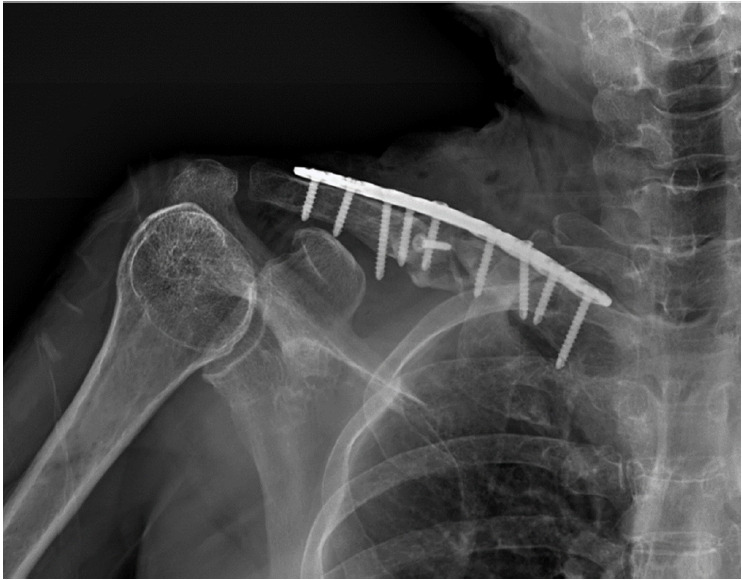

Brachial plexus paralysis is a rare but serious complication following clavicle fractures that is often linked to neurovascular compression, with an incidence of 0.5% to 9.0%. This report presents a case of brachial plexus paralysis in a 61-year-old woman after surgical fixation of a deformed mid-clavicle fracture with a metal plate. Revision surgery was performed to address the paralysis, involving removal of the metal plate, arcuate osteoplasty to create a smooth arch beneath the clavicle, and re-fixation of the plate with adjusted superior angularity. We used this approach to relieve neurovascular compression and restore thoracic outlet space. Over a period of 1 year, significant recovery and successful fracture union were achieved. This case demonstrates that managing brachial plexus paralysis with revision surgery and osteoplasty can effectively restore both neurological function and bone healing.